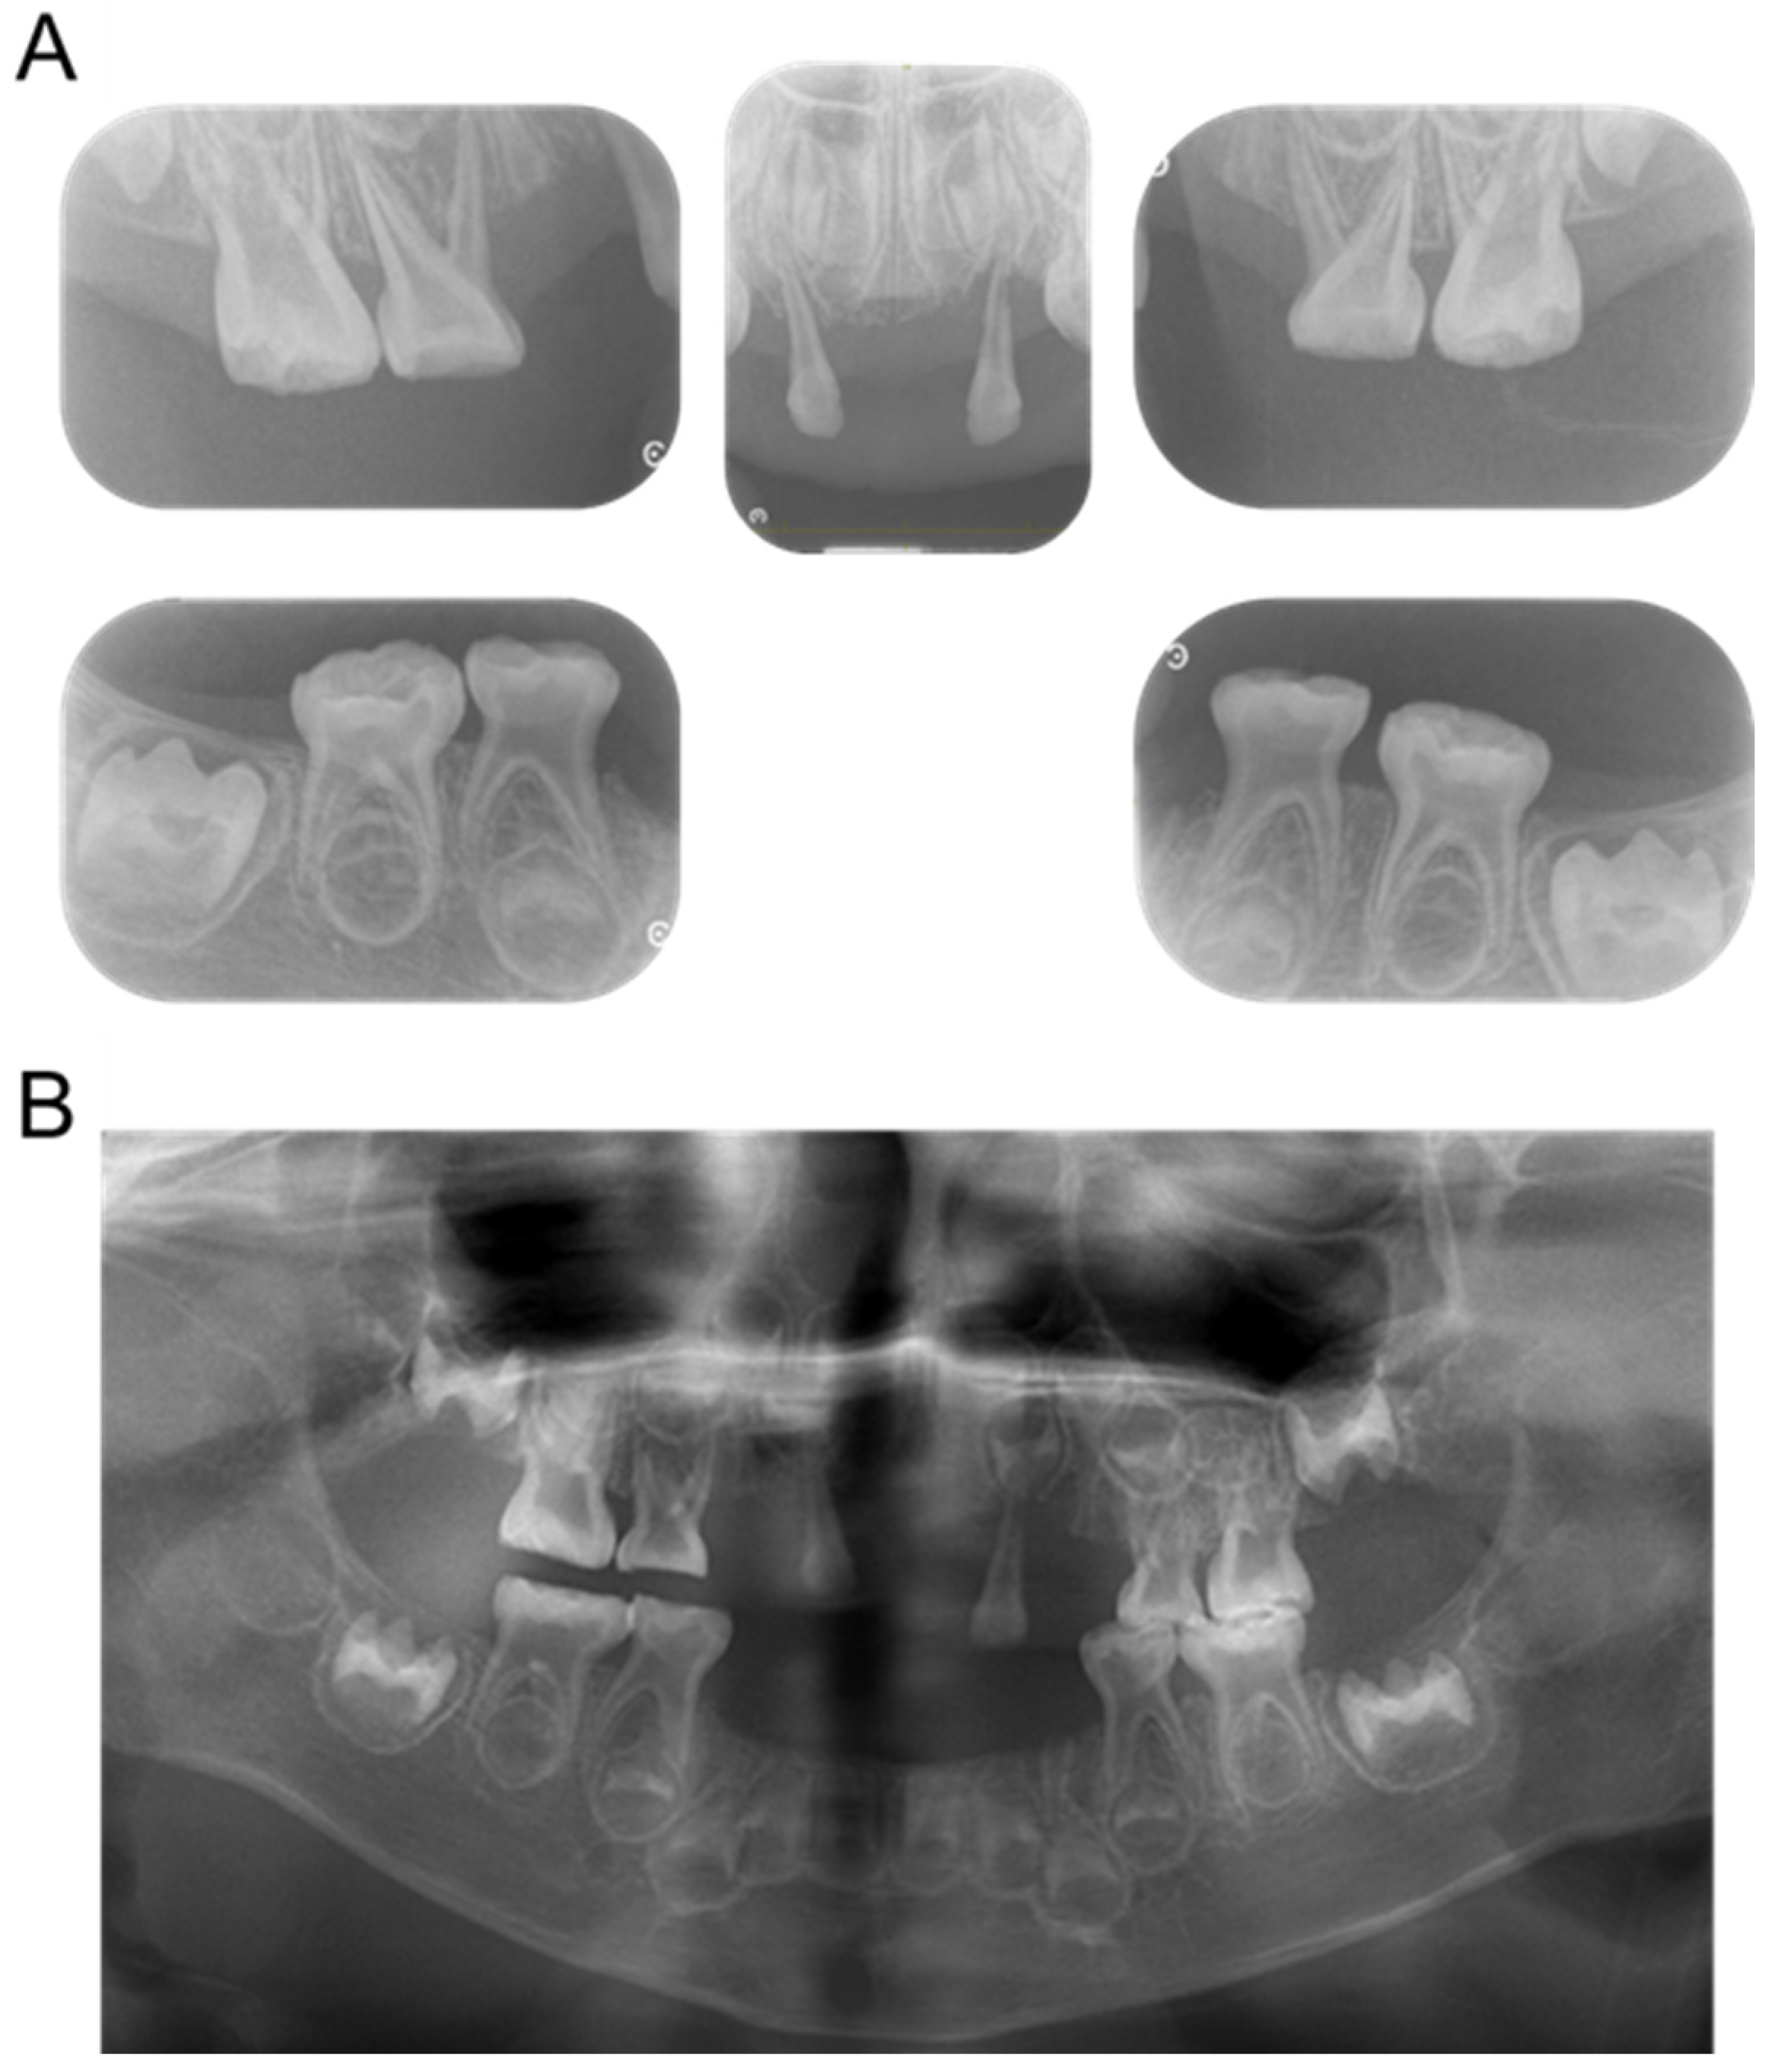

| Tooth | Time |

|---|---|

| Mandibular left primary central incisor | 1 year and 3 months |

| Mandibular right primary central incisor | 1 year and 7 months |

| Mandibular left primary lateral incisor | 2 years |

| Mandibular right primary lateral incisor | 2 years and 4 months |

| Maxillary right primary canine | 2 years and 7 months |

| Mandibular right primary canine | 2 years and 8 months |

| Maxillary right primary central incisor | 3 years |

| Maxillary left primary canine | 3 years |

| Maxillary left primary central incisor | 3 years and 9 months |

| Mandibular left primary canine | 4 years and 3 months |

| Maxillary left primary lateral incisor | 4 years and 6 months |